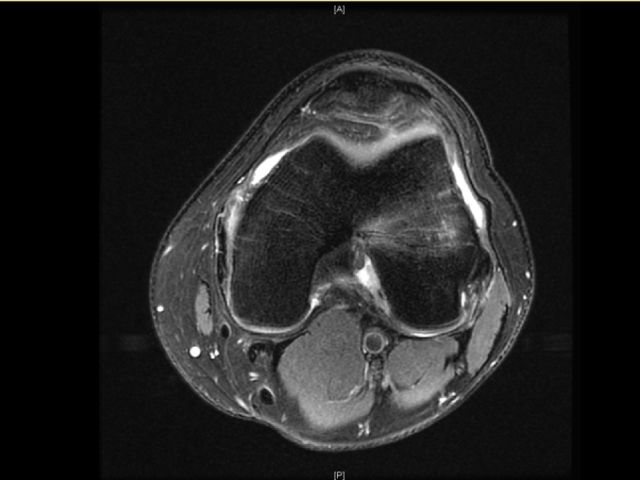

前交叉韧带断裂

从这个病例我们可以看到明显的股骨外髁骨擦伤,韧带的形态是中断的,大片的渗出病变,并且以胫骨平台的夹角变小,下止点可见部分信号增高,上止点可见大片的渗出病变,缺乏韧带止点应有的形态和张力,轴位片也可以看到内外上止点信号改变。所以这个病例考虑前交叉韧带断裂。